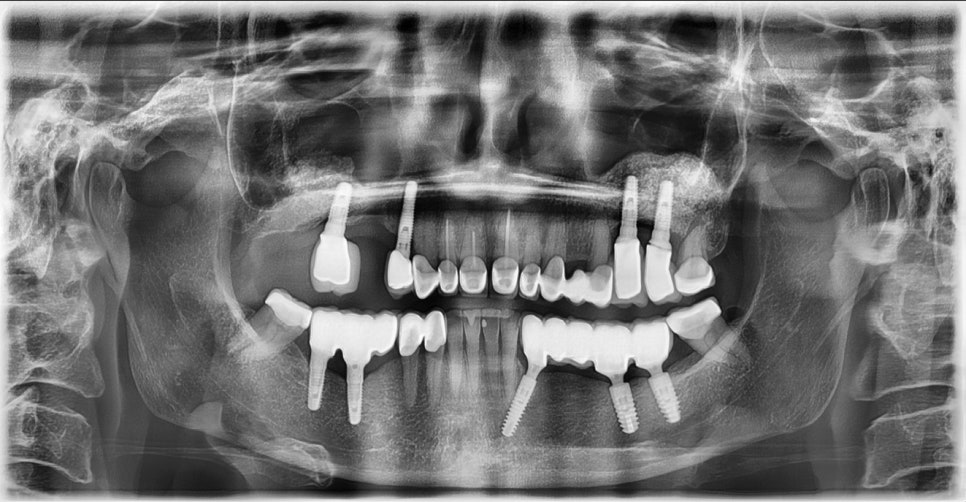

2026.1 초진 파노라마 사진 - 연세정원치과

기존 보철물 자체는 비교적 양호했으나, 오랜 시간이 지나면서 잇몸이 서시히 올라가 치아 뿌리가 노출되었고, 드러난 뿌리에 마모가 진행되며 심미적인 문제뿐 아니라 치아 건강 측면에서도 크라운 재치료가 필요해 보였습니다.